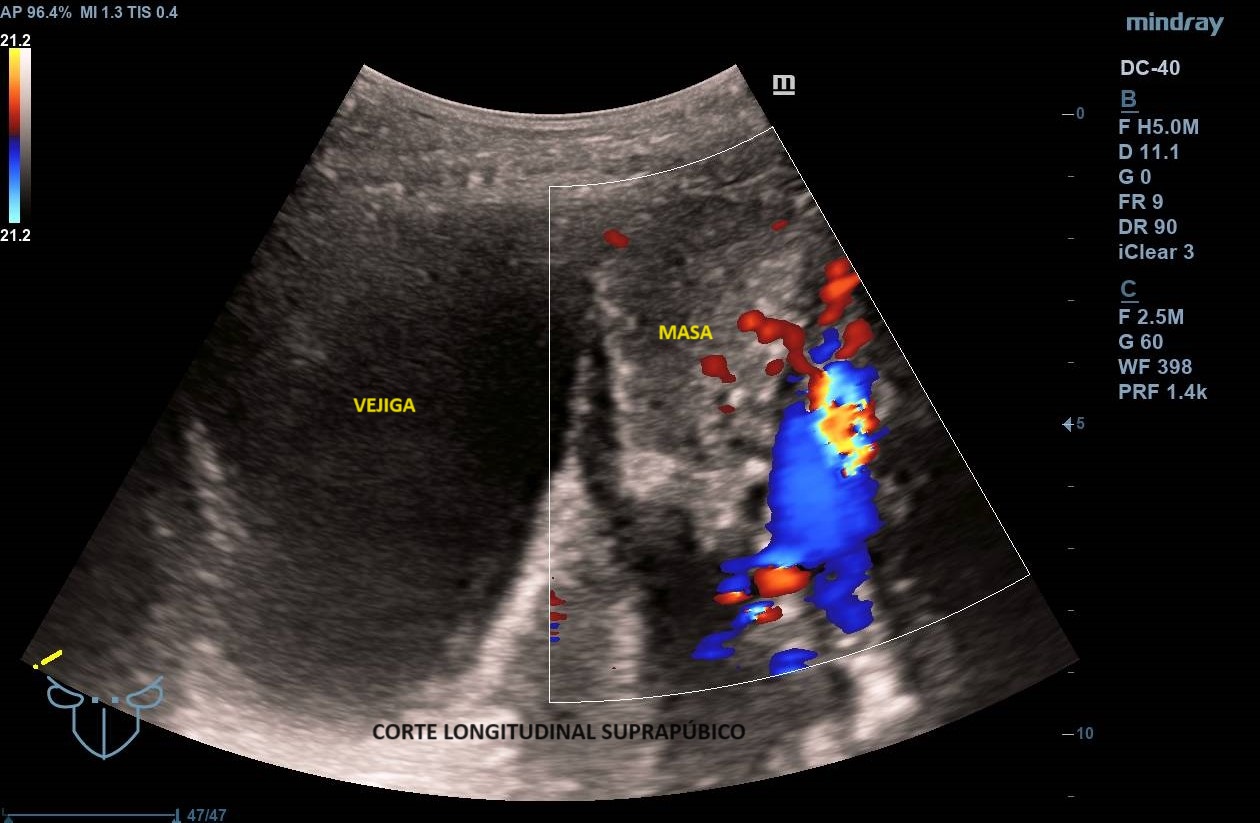

Ecografía abdominal clínica: Masa heterogénea que ocupa todo el abdomen, de aspecto sólido, vascularizada con zonas hipoecoicas-anecoicas en su interior. Riñones con eco-estructura sin alteraciones, hígado sin LOES. Vejiga sin engrosamiento de paredes, útero parcialmente visible. Anejos y retroperitoneo no valorables. No líquido libre.

Se deriva a urgencias donde realizan ecografía transvaginal confirmando presencia de masa que parece depender de anejo derecho. Solicitan TAC toraco-abdomino-pélvico objetivando «masa abdominal gigante de dudosa dependencia ovárica, no pudiendo descartar liposarcoma abdominal». Citan a la paciente para RM donde se demuestra contacto pero no dependencia de masa abdominal, probable liposarcoma, de anejo derecho, de características normales. Analítica con marcadores tumorales sin alteraciones.

Los leiomiomas uterinos son el tumor más frecuente de pelvis en la mujer. La ecografía es la primera línea de estudio. Habitualmente s

e describen como masas bien delimitadas redondeadas hipoecoicas con sombra acústica, aunque también pueden tener áreas isoecoicas e hiperecoicas. Pueden presentar necrosis central (áreas anecoicas) o calcificaciones, sin implicar malignización. El Doppler-color suele mostrar una distribución irregular de los vasos. El diagnóstico definitivo es el anatomo-patológico.